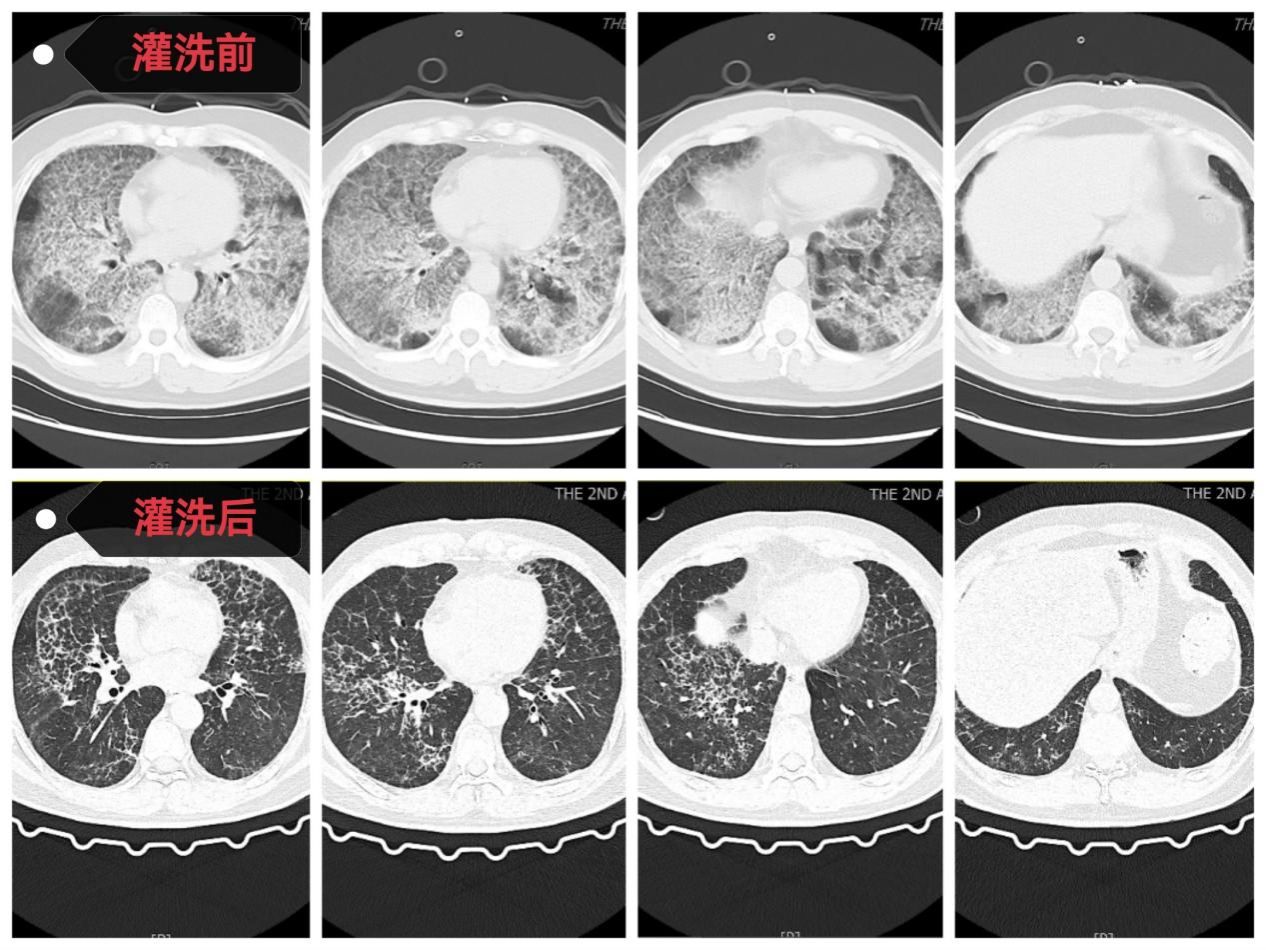

方萍主任医师团队与患者家属进行充分沟通并取得支持后,一场多学科协作的生命保卫战打响。首先,麻醉科雷晓鸣主任医师和宋正川副主任医师团队为患者实施全麻下双腔气管插管有创呼吸支持,随后呼吸与危重症医学科和急诊科ECMO团队(呼吸与危重症医学科方萍主任医师、邓文静主治医师、樊娜主治医师、刘勇护士、韩青青护士以及急诊科冯辉主治医师等)立即为患者建立VV-ECMO通路并顺利转机,患者氧合情况迅速稳定。随后,手术台上,方萍主任医师、黎蒙护士以及手术室多名医护人员紧密配合,共使用20000毫升37℃生理盐水为患者进行双肺“深度清洁”。灌洗回收液从最初的浑浊“牛奶状”逐渐变得清澈,回收率>90%,快速直观地展现了灌洗的效果。

术后,患者在ECMO支持下转入呼吸与危重症医学科RICU继续治疗。在长达11天的ECMO支持期间,RICU医护团队日夜坚守,严密监测,精准调整抗感染、抗凝策略和ECMO、呼吸机支持参数。随着患者自身肺功能逐渐改善,复查血气指标显著好转,胸部CT显示双肺弥漫性阴影较入院时明显吸收。最终成功撤除ECMO,并顺利脱离呼吸机、拔除气管插管。出院时,患者在不吸氧的情况下,血氧饱和度维持在正常水平,活动能力恢复,实现了从“命悬一线”到“行动自如”的生命奇迹。

全肺灌洗前后影像资料对比